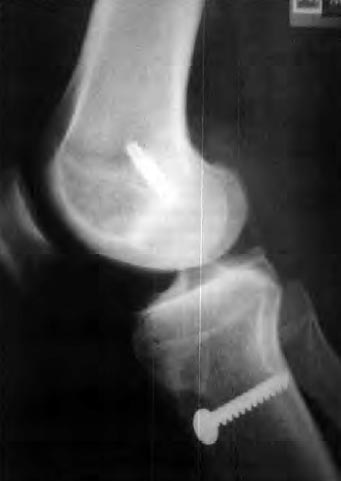

Las formas de los túneles tibiales fueron definidas en dibujos realizados en papel transparente sobre las radiografías y separadas en grupos (Tabla 4): túneles en forma de cono con base proximal (T 1), túneles con el tercio central ensanchado (T2) y túneles en forma de cilindro (T3) (Fig. 3). Se consideraron solamente los túneles donde había buena definición completa de bordes en las radiografías. Los porcentajes se calcularon en relación al número total de pacientes de cada grupo.

Figura 3: Radiografías en antero-posterior y perfil mostrando túneles en forma de cono con base proximal (Ti), túneles con el tercio central ensanchado (T2) y túneles en forma de cilindro (T3).

En la tabla 4. los resultados muestran que los túneles tienen formas diferentes en las radiografías en AP y P. Las radiografías en perfil definen mejor la forma de los túneles. En las radiografías en perfil del grupo 1, el 59,52% presentaban túneles de forma cónica. En el grupo 2, la forma cónica (4 1 ,86%) tcxiavía es predominante, pero la forma cilíndrica ya representa el 30,23%. En el grupo 3. la forma cilíndrica representa el 51,22%.

En este trabajo se encontraron las mismas formas de ensanchamiento. Se supone que la absorción de las paredes del túnel puede ocurrir en áreas de mayor movimiento del tendón en relación al túnel. Por lo tanto, en los túneles en forma de cono (Ti) habría mayor movimiento en el 1/3 proximal del túnel. En los túneles en forma de cavidad (T2), en el área central y en los túneles de forma cilíndrica o línea (T3), el movimiento sería mínimo y homogéneamente distribuido en todo el túnel. En los pacientes del Grupo l predominó la forma de cono, lo que muestra que la fijación distal del injerto produjo un ensanchamiento proximal mayor en el sentido antera-posterior. En el Grupo 2a todavía persiste esta tendencia. En el Grupo 2h esta tendencia se invierte con los túneles siendo predominantemente cilíndricos. Creemos que la diferencia entre el Grupa 2a y 2b se debe a la forma del tornillo, más que a factores biológicos. Los tornillos absorvibles Arthrex@ son cilíndricos y ocuparían de forma homogénea el espacio entre el tendón y la pared ósea en los túneles. Los tornillos metálicos son cónicos y por lo tanto ocupan totalmente solo la parte distal del túnel tibial en tesis permitiendo movimiento en el 1/3 proximal. Tres de esos tornillos metálicos eran cilíndricos y en esos túneles el ensanchamiento fue cilíndrico, pero el número de pacientes fue pequeño para que la conclusión pudiese considerarse estadísticamente válida.